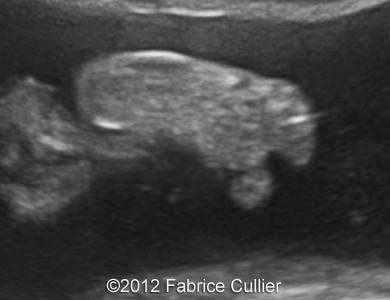

Image 3, 4, 5: An abnormally thick corpus callosum.

1C

1D

1F